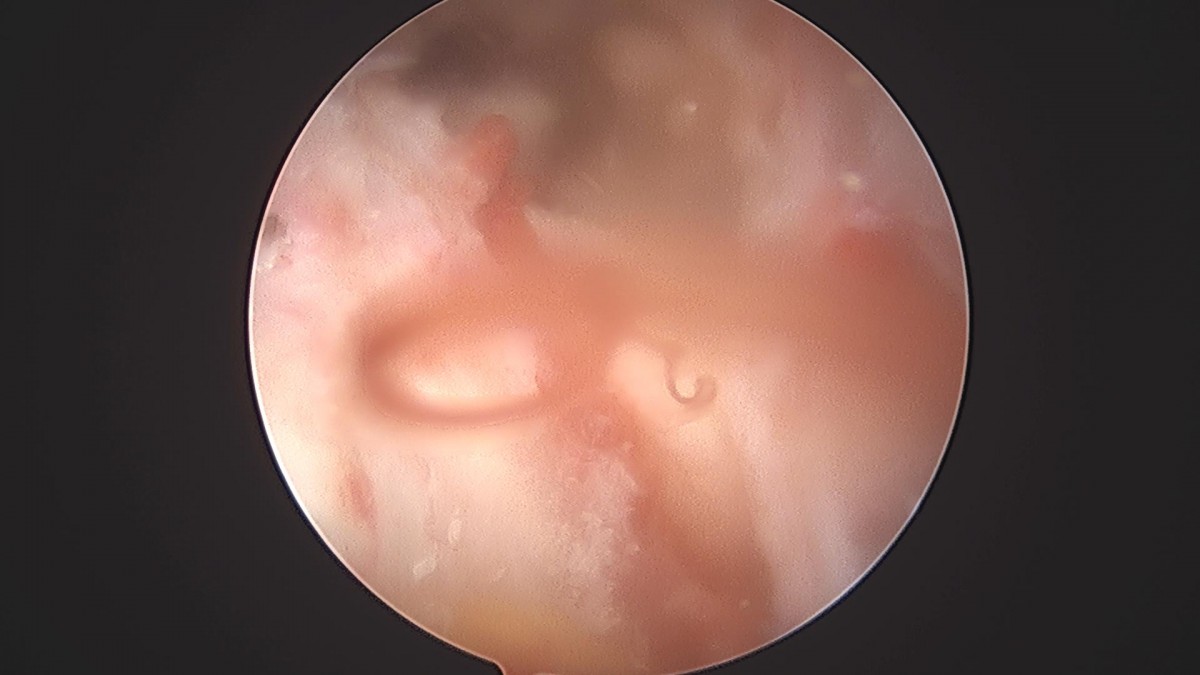

이재상원장님 어깨 견봉하감압술 및 이두박건절제술 류창O 환자